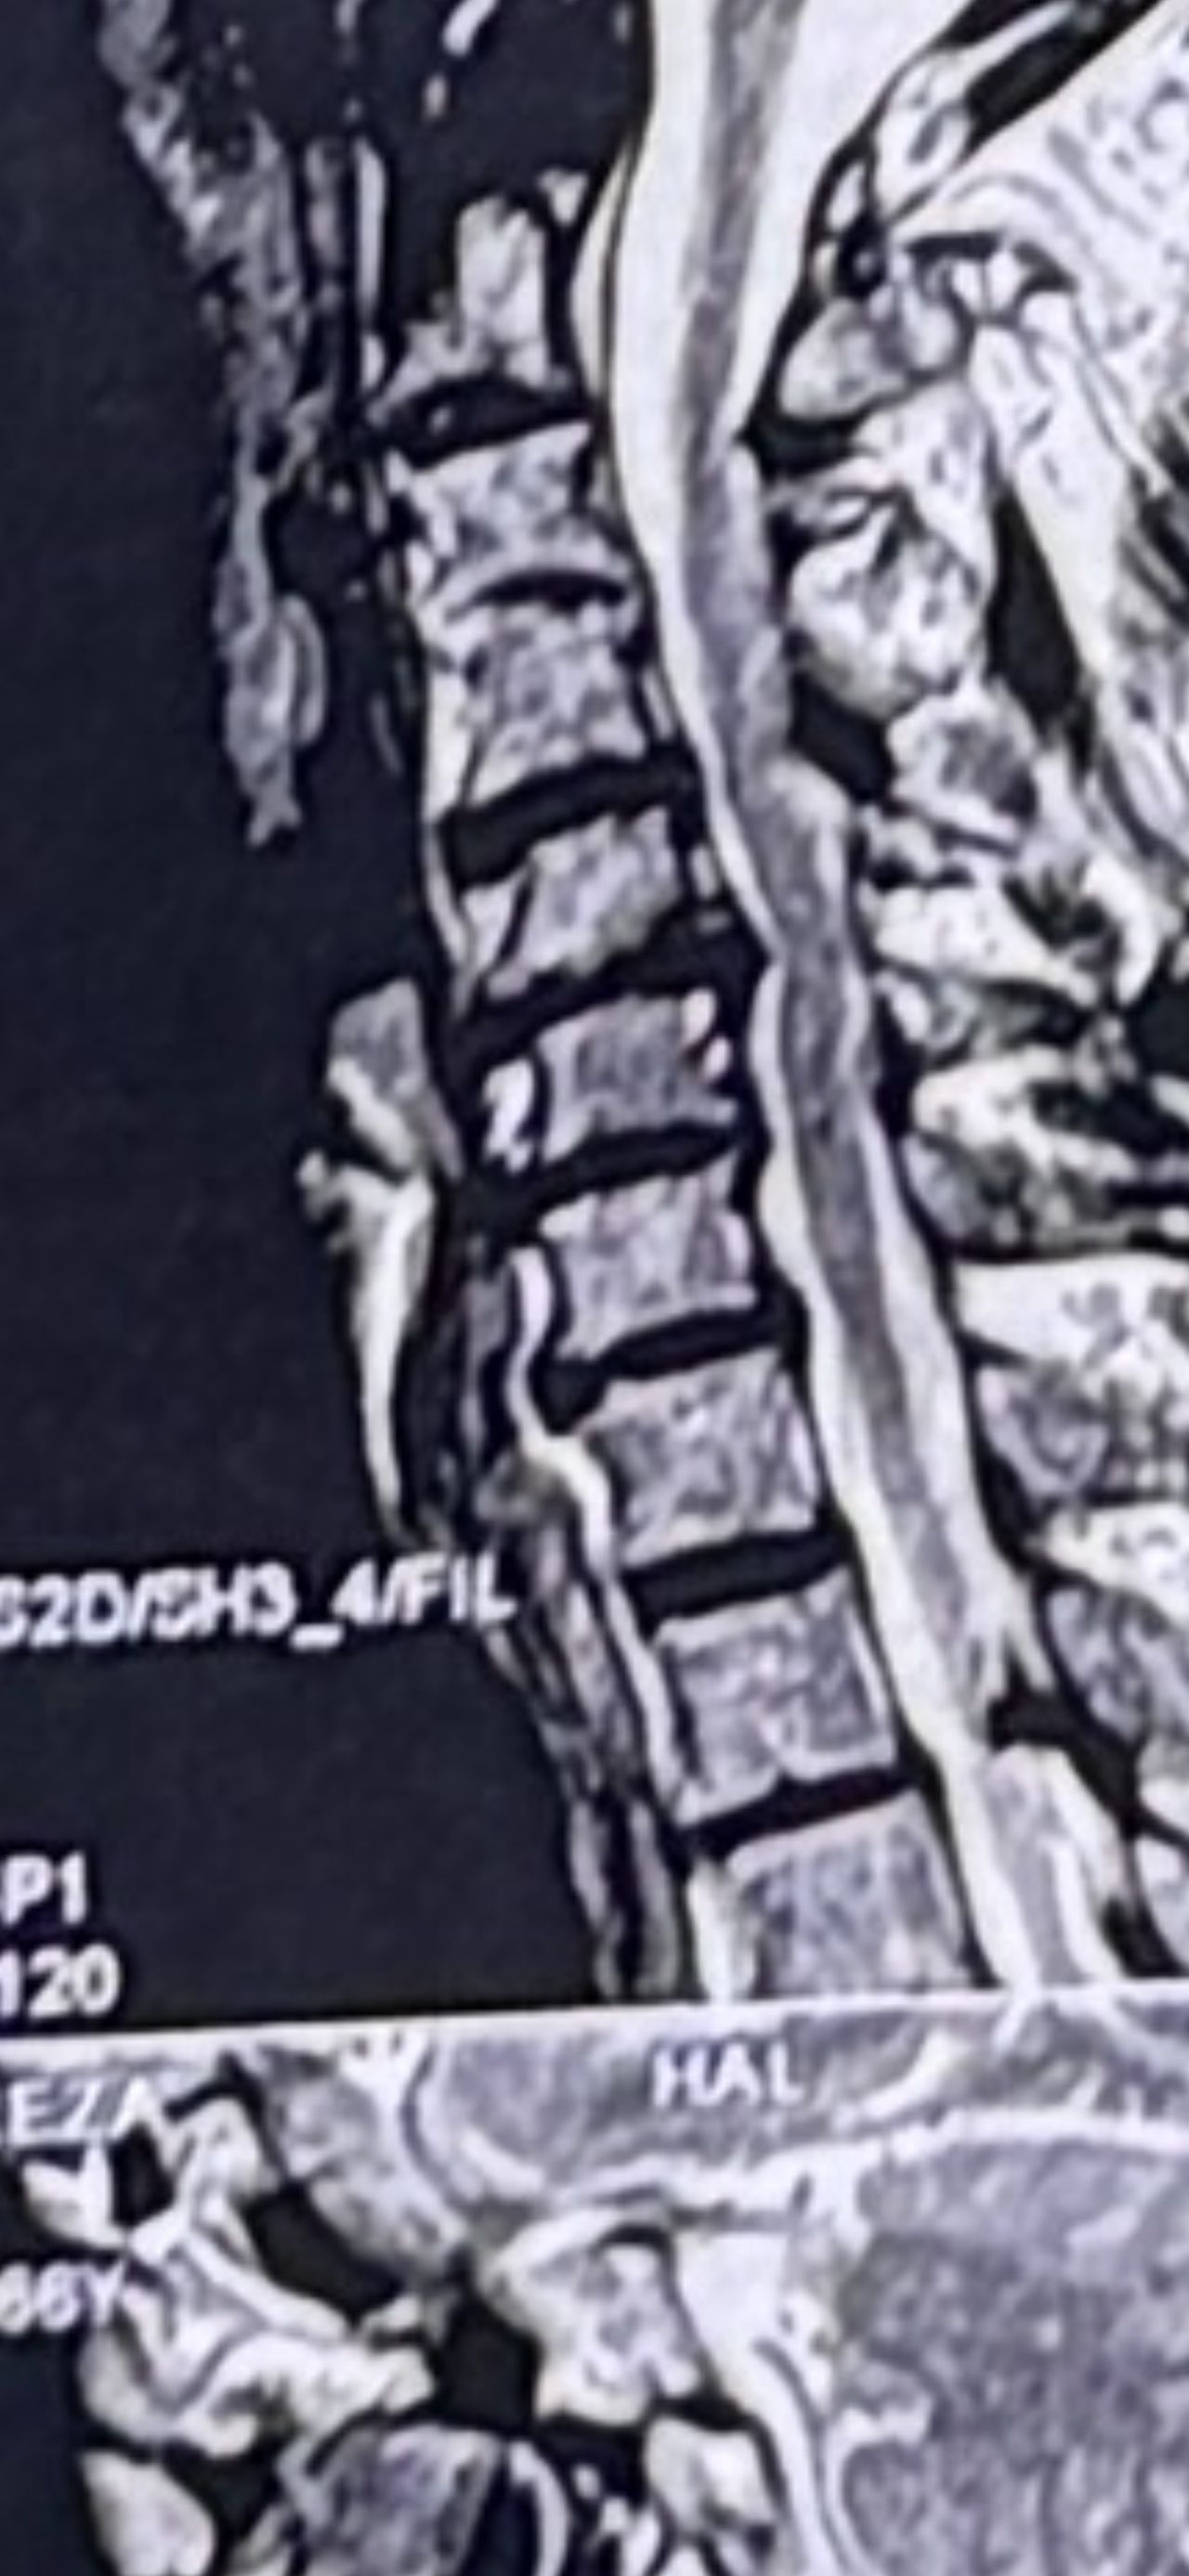

41 years old man presented to my clinic in October 2023 with acute and sever R neck pain with radicular pain to his R upper extremity along C6 dematom since 2 weeks ago. Examination didn’t show any upper motor signs. Was suggested urgent surgery

I ordered EMG/ NCV : showed mild R C6, C7 irritation without any active axonal loss

In his MRI was reported R. para R. IVF Massive extrusion. I decided to control his pain and manage this patient with reevaluation of patient every other session. For 5 sessions i just used acupuncture and laser and IFC and mild adjustments to his R. T3-T7 and mild arthosteem to above and below involved segment. Cervical adjustment considered contraindicated for this patient. From session 6th- 8th i started to use mild/gentle cervical decompression. He used soft cervical collar all the time. His pain decreased by 80 percent

I gave him cervical traction pump to be used 3-5 times per day at home for the next 3 months and i released the patient. He was evaluated every week once for one month and after that every 2 weeks. After 3 month I repeated MRI. Size of the herniated disc was reduced greater than 50 percent. Asked him to do another mri in 6 months

In general: Precise selection of the patients, examination,diagnosis, plan of management, reevaluation and treatment can be done by doctors of chiropractic for the patients with spinal disc herniation and stenosis Moreover giving reasonable time to these kind of patients under direct supervision by their chiropractic doctors can prevent unnecessary surgery. Proper selection of these kind of patients is another important fact that can be done precisely by chiropractors.

MRIs before and after proper management of this patient: